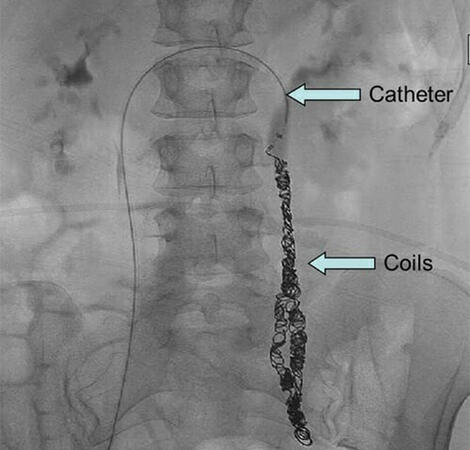

Εμβολισμός:

Ο εμβολισμός με καθετηριάζουσα επέμβαση είναι μια ελάχιστα επεμβατική διαδικασία όπου ένα καθετήρας εισάγεται στις επηρεασμένες φλέβες, και μικροσκοπικά έμβολα σε συνδυασμό με σκληρυντικό αφρό χρησιμοποιούνται για τον αποκλεισμό των κιρσοειδών φλεβών, ανακατευθύνοντας τη ροή του αίματος. Συχνά, αυτή η διαδικασία είναι αποτελεσματική στην ανακούφιση των συμπτωμάτων.